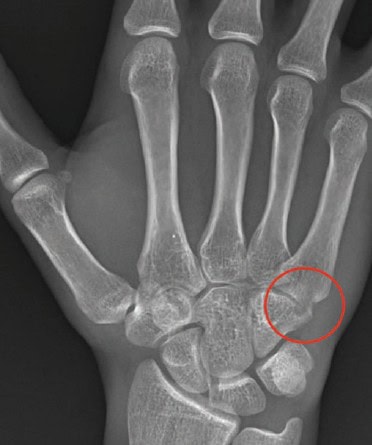

The correct diagnosis is a hamate fracture, which is the third most common type of hand fracture. Among these, fractures of the hook of the hamate are more frequent than those involving the body of the bone. This injury often occurs either from a fall onto an outstretched hand or during sports activities when the end of a club, racquet, or bat is driven into the palm, applying direct pressure to the hypothenar eminence. It can affect either the dominant or non-dominant hand. Chronic, high-tension gripping may also contribute to the development of this fracture.

- On x-ray imaging, you may see subtle hypodensity and cortical indistinctness of the hamate bone, but plain films have poor sensitivity and specificity for hamate fracture.